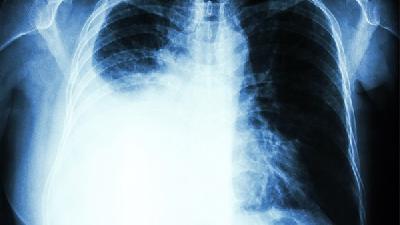

大家都知道导致肺癌的主要原因是吸烟,而且高发于男性群体,对于肺器官的损害非常大。然而很多人不了解肺癌的具体发病症状,很多患者患病了还以为是平时的感冒等症状,导致肺癌没有得到及时的治疗,使病情加重。下面将具体介绍一下肺癌的症状表现。